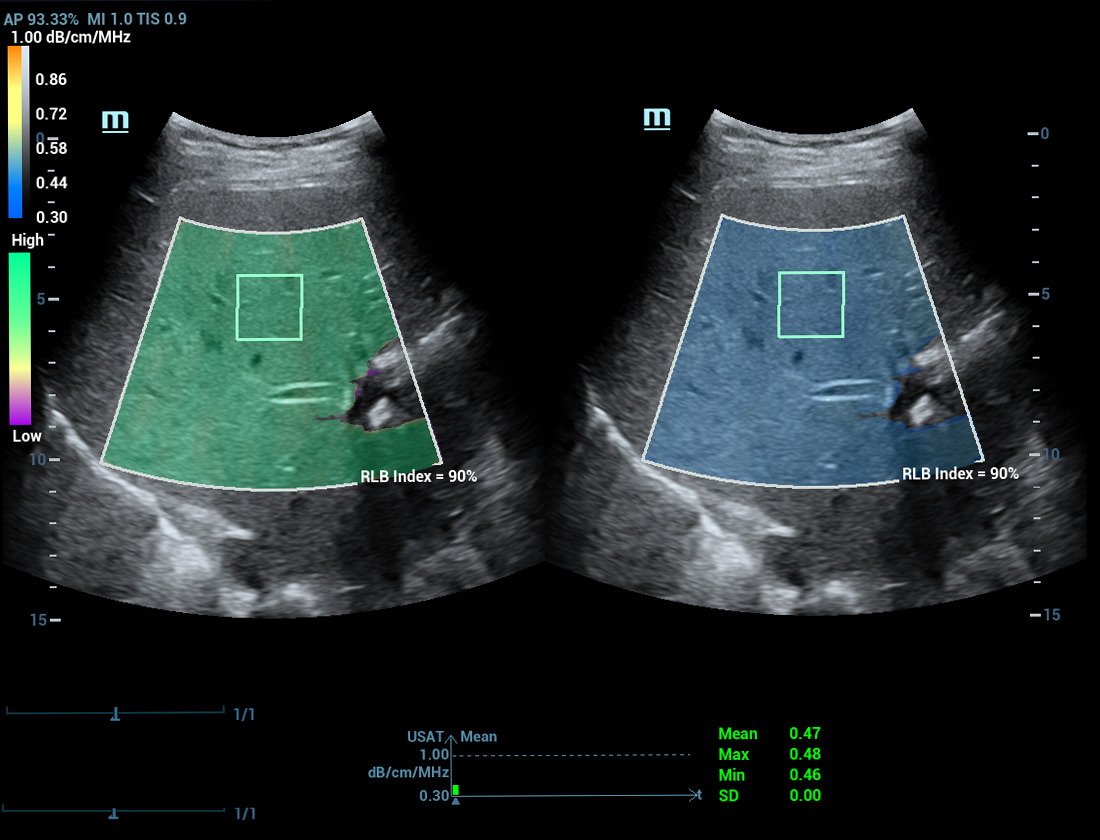

Laboratû°rio multiparamûˋtrico de fûÙgado gorduroso

Um novo salto para a pesquisa sobre esteatose

Laboratû°rio multiparamûˋtrico de fûÙgado gorduroso

O laboratû°rio multiparamûˋtrico de fûÙgado gorduroso oferece vûÀrias ferramentas de anûÀlise quantitativa baseadas em diferentes tecnologias. Permite a anûÀlise quantitativa da esteatose e melhora a sensibilidade na detec??o de fûÙgado gorduroso em estûÀgio inicial.

USAT S0